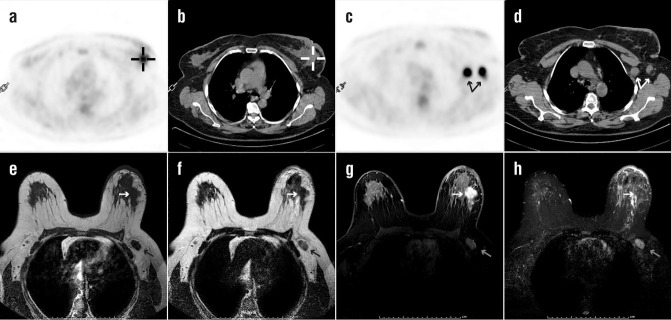

Objectives: Breast carcinoma is the most common type of cancer in females. This study aims to compare fluorine-18-fluorodeoxyglucose (18F-FDG) uptake pattern and apparent diffusion coefficient (ADC) value for the detection of the primary tumour and axillary metastases of invasive ductal breast carcinoma.

Methods: This study included 40 breast carcinoma lesions taken from 39 patients. After staging by positron emission tomography-computed tomography (PET/CT) and diffusion-weighted magnetic resonance imaging (MRI), breast surgery with axillary lymph node dissection or sentinel lymph node biopsy was performed.

Results: Primary lesion detection rate for PET/CT and diffusion-weighted MRI was high with 39 of 40 lesions (97.5%). The sensitivity and specificity for the detection of metastatic lymph nodes in axilla were 40.9%, 88.9%, with 18F-FDG PET/CT scans and 40.9%, 83.3%, for dw-MRI, respectively. No significant correlation was detected between ADC and SUVmax or SUVmax ratios. Estrogen receptor (p=0.007) and progesterone receptor (p=0.036) positive patients had lower ADC values. Tumour SUVmax was lower in T1 than T2 tumour size (p=0.027) and progesterone receptor-positive patients (p=0.029). Tumour/background SUVmax was lower in progesterone receptor-positive patients (p=0.004). Tumour/liver SUVmax was higher in grade III patients (p=0.035) and progesterone receptor negative status (p=0.043).

Conclusions: This study confirmed the high detection rate of breast carcinoma in both modalities. They have same sensitivity for the detection of axillary lymph node metastases, whereas the PET/CT scan had higher specificity. Furthermore, ADC, SUVmax and SUVmax ratios showed some statistical significance among the patient groups according to different pathological parameters.